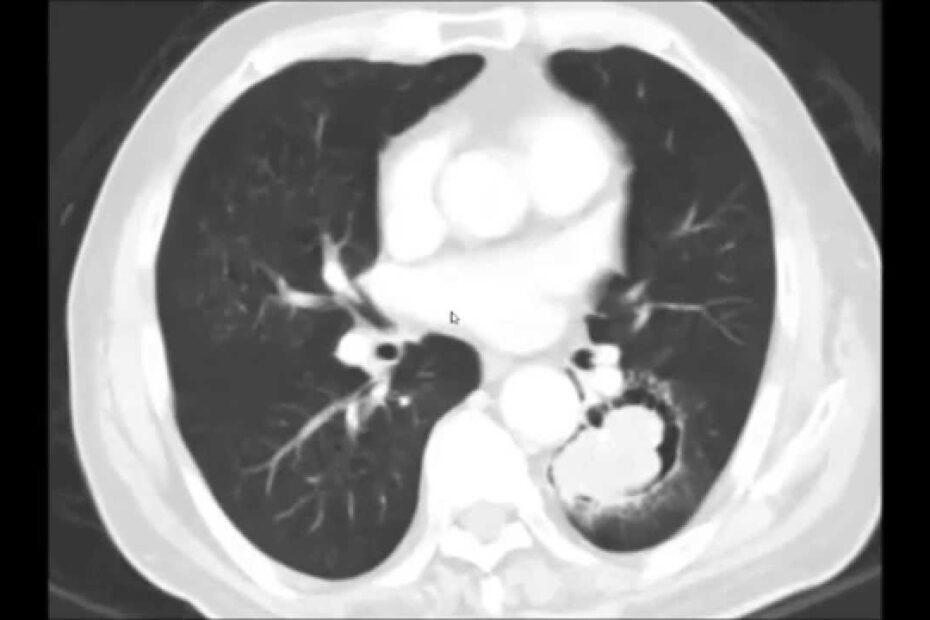

pulmão